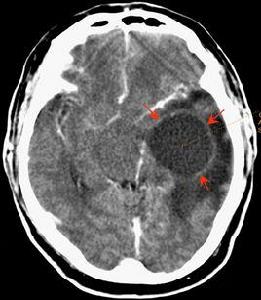

腦瘤 顱內腫瘤即各種腦瘤,是神經系統中常見的疾病之一,對人類神經系統的功能有很大的危害。一般分為原發和繼發兩大類。原發性顱內腫瘤可發生於腦組織、腦膜、顱神經、垂體、血管殘餘胚胎組織等。繼發性腫瘤指身體其它部位的惡性腫瘤轉移或侵入顱內形成的轉移瘤。

顱內腫瘤可發生於任何年齡,以20-50歲為最多見。少兒以顱後窩及中線腫瘤較多見,主要為髓母細胞瘤,顱咽管瘤及室管膜瘤。成人以大腦半球膠質瘤為最多見,如星形細胞瘤、膠質母細胞瘤、室管膜瘤等其次為腦膜瘤、垂體瘤及顱咽管瘤、神經纖維瘤、海綿狀血管瘤、膽脂瘤等。原發性顱內腫瘤發生率無明顯性別差異,男稍多於女。

1.星狀細胞瘤(Astrocytoma): 是最常見的膠質瘤,占膠質瘤的40%,可生長在腦或脊髓內的任何地方。成人的星狀細胞瘤大多長在大腦,而兒童的星狀細胞瘤則常長在小腦及腦幹。就腫瘤的惡性度而言,可分為四級如下: 第一級-毛狀星細胞瘤(Pilocytic Astrocytoma)第二級-星細胞瘤(Astrocytoma)屬低惡性腫瘤,第三級-分化不良星細胞瘤(Anaplastic Astrocytoma; AA)第四級-多形性膠質母細胞瘤(Glioblastoma Multiform; GBM)屬惡性腫瘤。